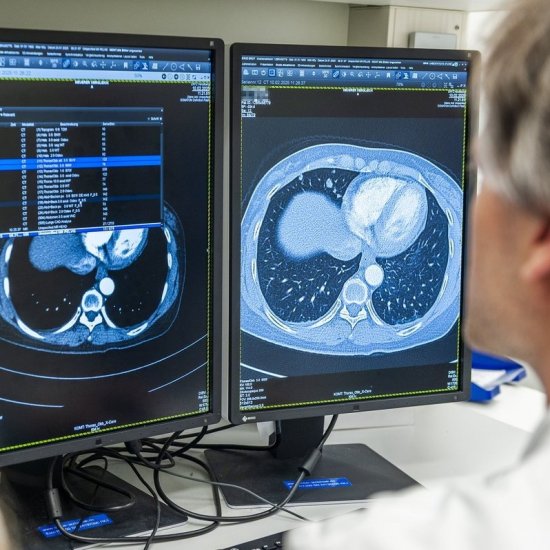

News • Risikoadaptierte Strategie

Ehemalige starke Raucher haben ein erhöhtes Risiko für Lungenkrebs – doch ein pauschal früheres Screening wird dem individuellen Risikoprofil nicht gerecht. Eine neue Strategie soll das ändern. |